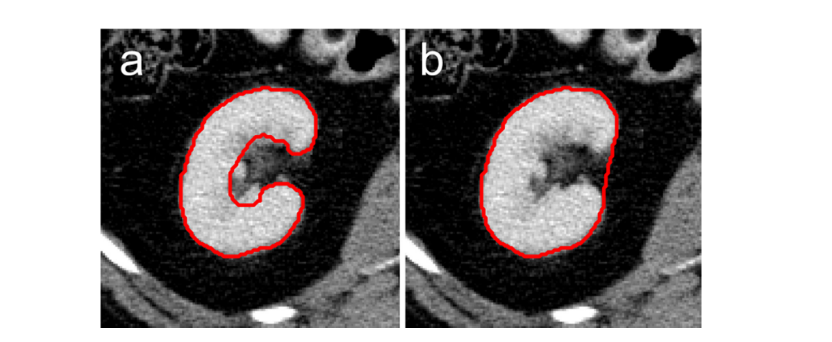

Figure 6展示了不同级别的肾区域分化的准确度对比图。a图展示了本研究采用的高分辨率分段方法,并特意排除了肾盂及其血管部分;b图则呈现了相对粗略的分段效果

图表 6展示了不同细分粒度下肾脏解剖结构的分割精度比较。a组采用了更为精细的空间细分策略,在不考虑肾盂及其相关血管组织的前提下完成了对主肾体腔区域(约55-75mm)以及主肾支管(约135-145mm)的空间定位;b组则采用了较为粗略的空间细分策略,在上述区域的基础上增加了对肾盂及其相关血管组织的部分解剖细节描述